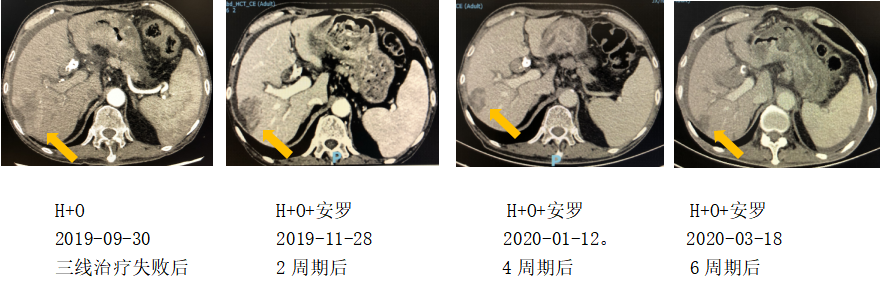

治疗经过:四线治疗

具体治疗方案:

纳武利尤单抗140mg;

赫赛汀6mg/kg,

安罗替尼10mg D1-14

每3周重复。

2020-09电话随访,患者于当地医院继续行赫赛汀+纳武利尤单抗+安罗替尼方案治疗中,肿瘤控制稳定

对于晚期胃癌而言,目前化疗已进入瓶颈期,通过化疗药物或化疗方案的改善,很难有进一步的提升空间。胃癌靶向药物的研究也在艰难中缓慢进展。免疫治疗是目前能够带来惊喜的一个非常有前景的方向,也是后续胃癌治疗中一个非常重要的研究方向。免疫治疗单药有效率偏低,免疫联合治疗是一个非常重要的模式,或与化疗联合,或是与化疗、靶向联合。何种联合模式是最佳联合模式,在哪个阶段介入免疫治疗是最好的时机,这些都需要我们在未来进行更多的研究和探讨。在本例患者后续的治疗中,在赫赛汀加免疫治疗失败后,我们尝试加上小分子抗血管药物安罗替尼,肿瘤明显缩小,病情得到控制,给患者带来一个较长的生存期,可见得一方面坚持抗HER2治疗,另一方面加上小分子抗血管药物可能是一个较好的搭挡,值得未来更多的探讨。